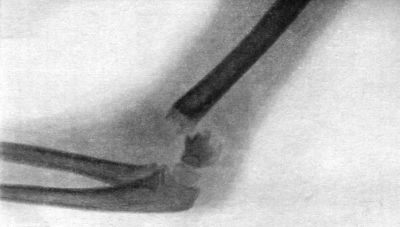

| 38. | Radiogram of Incomplete Backward Dislocation of Elbow | 91 |

| 39. | Forward Dislocation of Elbow, with Fracture of Olecranon | 93 |

| 40. | Radiogram of Forward Dislocation of Head of Radius, with Fracture of Shaft of Ulna | 95 |